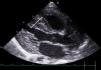

The cardiological evaluation detected severe left ventricular systolic dysfunction with an ejection fraction of 37%. The patient received support with milrinone and furosemide and responded well, with resolution of metabolic acidosis and a decrease in lactate levels to less than 5 mmol/L. The dose of milrinone could be tapered off and eventually discontinued after initiation of carvedilol. Later on, captopril was added and maintained until hospital discharge.

The standardised echocardiographic assessments evinced normalisation of systolic function in both ventricles and structural improvement, albeit with persistent thickening of the left ventricle and trabeculation in the right ventricle (Fig. 1).